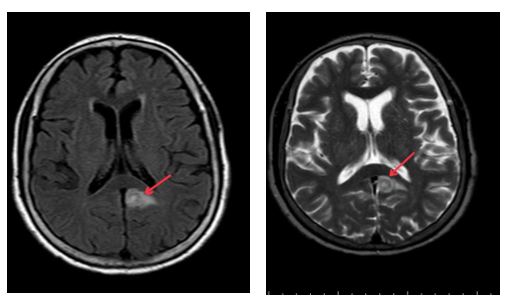

- Cộng hưởng từ sọ não: Nhu mô bán cầu tiểu não trái và thuỳ đỉnh trái cạnh thể trai có tổn thương tăng tín hiệu trên FLAIR, ngấm thuốc viền sau tiêm, phù não rộng xung quanh, kích thước 11x12mm và 7mm (theo dõi thứ phát). Nhu mô chất trắng cạnh não thất bên và trung tâm bán bầu dục hai bên có vài nốt thoái hoá myelin chất trắng, đường kính <5mm

Hình 2: Cộng hưởng từ sọ não lúc mới nhập viện: Tổn thương tăng tín hiệu trên FLAIR tại bán cầu tiểu não trái và thùy đỉnh trái cạnh não thất(mũi tên đỏ).